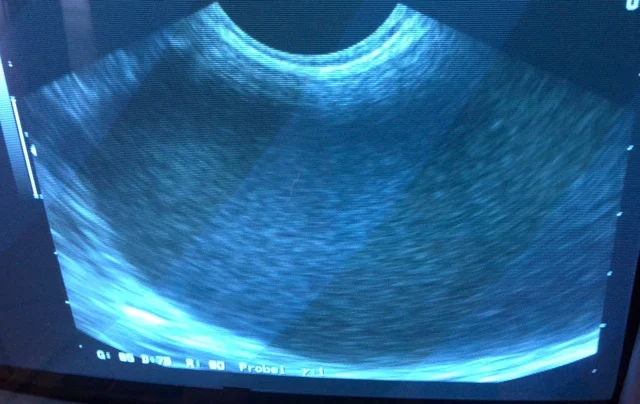

We did an ultrasound of her belly and found that it contained a large fluid filled structure.

Based on this finding and her history I was highly suspicious that Prescilla had a pyometron.